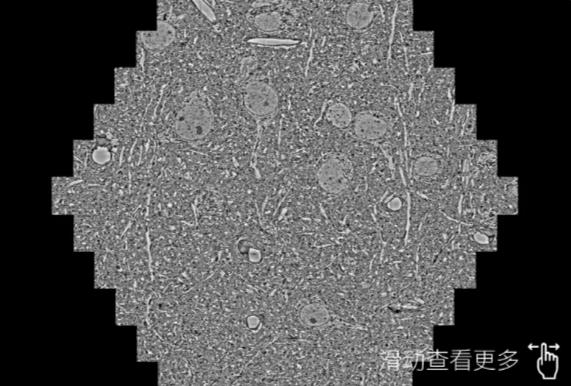

鼠脑切片。左图使用郴州蔡司郴州扫描电镜MultiSEM706对165μmx143pm面积区域成像,耗时仅需1.5秒。右图为鼠脑切片中30μm区域放大效果。样品由芝加哥大学B.Kasthuri提供。

使用蔡司高速郴州扫描电镜MultiSEM对1mm²人脑皮层组织进行高分辨成像,并对其中的各种细胞结构进行三维重构分析。左图展示了2x3mm²组织平面中锥体神经元的三维重构效果。右图显示了局部体积神经元三维重构。图像由哈佛大学chtman实验室提供,渲染图由D. Berger 制作。